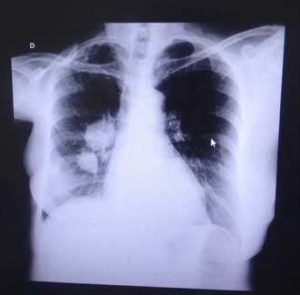

As in the case of other types, lung cancer does not have visible signs from the very beginning. Also, if diagnosed at an early stage, it can be mistaken for other illness with similar symptoms. This is what makes it so dangerous in comparison to other diseases. Chest radiographs and CT scans are the methods doctors use the most often, but a biopsy is needed to reach a conclusion. The majority of cases are diagnosed only when the disease has reached a final stage. At this point there is little to be done, mainly because the cancer is inoperable but also because the patient is old so surgery can only lead to more complications.

It is good to seek a doctor’s advice whenever one or more of these symptoms persist. The first tests include chest X-Ray films, CT scans, mediastinoscopy, which will be performed as soon as the specialist has the patient’s medical history. Afterward, more exams are to be conducted in various parts of the body to find out to which extent cancer has spread as well as its current stage. Although it is harder to cure, the small-cell carcinoma is rather responsive to chemotherapy and other treatments designed for patients suffering from it. In the situation when the illness is diagnosed faster, surgery might represent the right option, although it works best when combined with chemotherapy. Radiation is the most efficient way to impede the spread of malignant cells and kill the existing ones. SCLC is deadly for most patients, with the luckiest ones not living for more than five years after receiving a diagnosis.